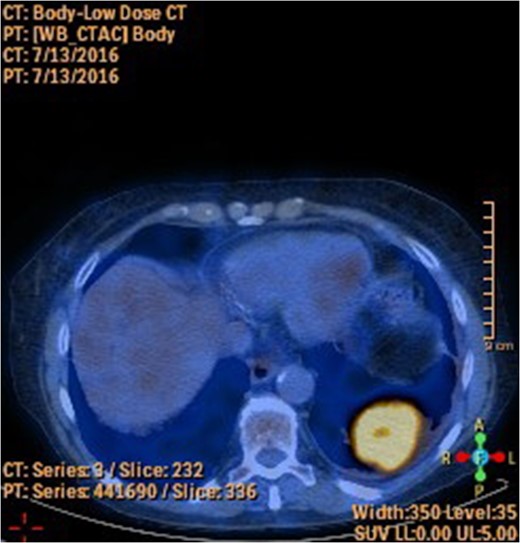

A 78-year-old female presented with worsening abdominal pain over 1 week, with onset of symptoms occurring 3 months prior. No history of recurrent fever or weight loss was elicited. There were no changes in bowel habits and she denied melena or hematochezia. She endorsed a normal colonoscopy three years prior. Of note, she was diagnosed with a biopsy proven squamous cell cancer of her left lower lobe 4 months earlier (Fig. 1). A PET scan performed just three weeks prior to her presentation demonstrated significant FDG uptake in the left lower lobe as well as the cecum, with no convincing evidence of regional nodal disease in the lungs (Figs 2 and 3).